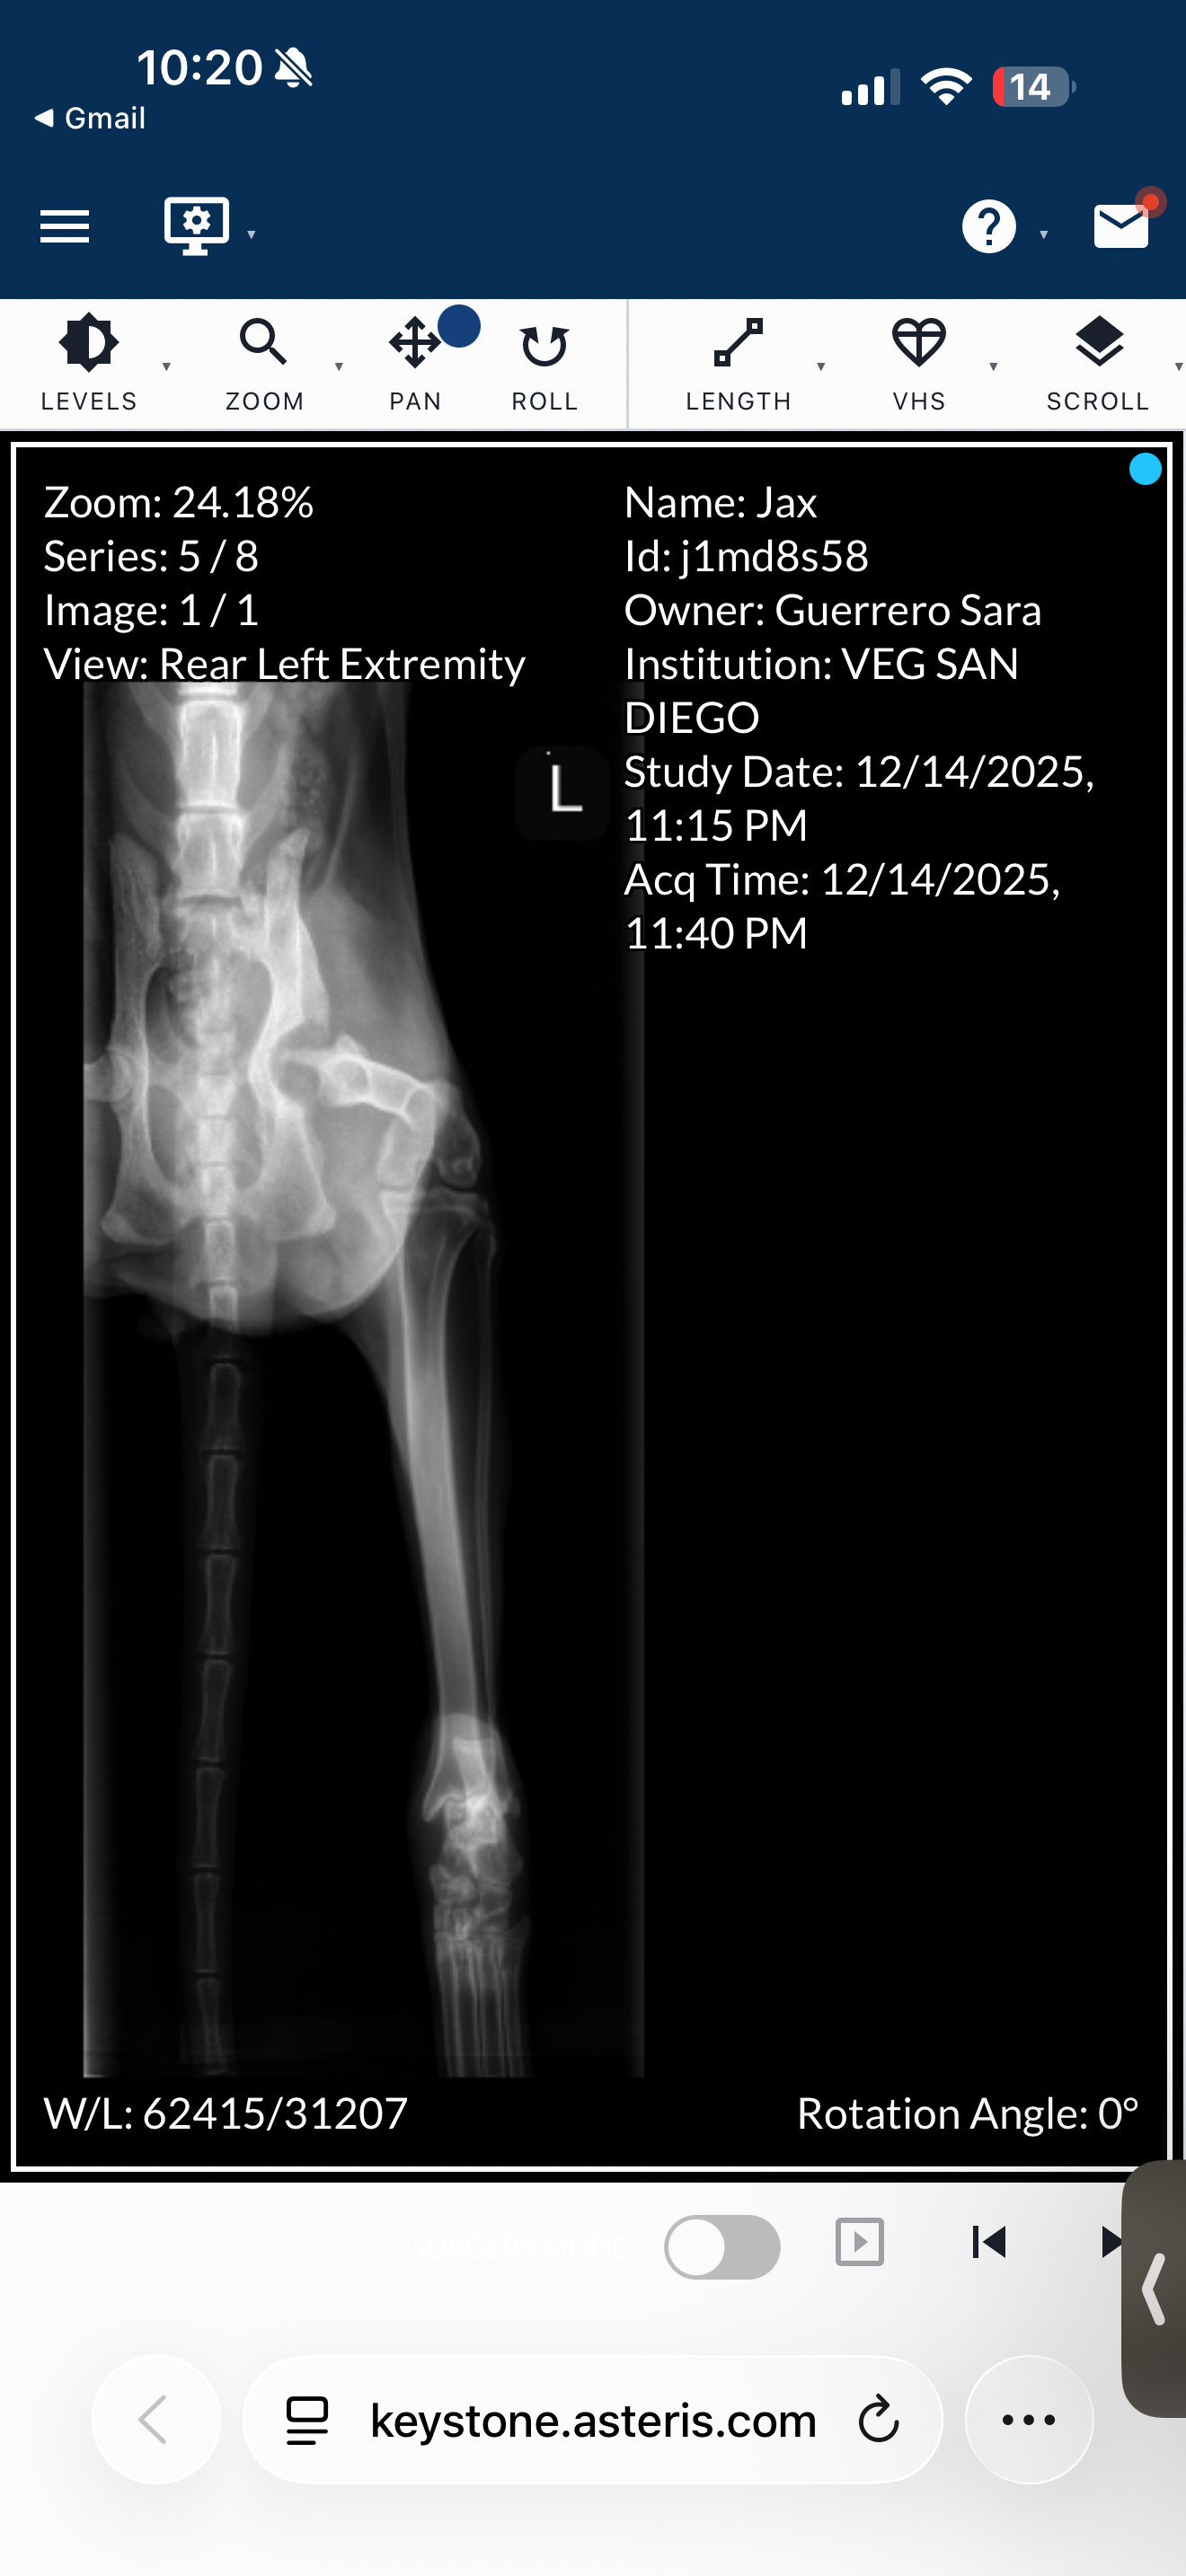

Recently, at the beginning of December, we noticed he had a limp on his left leg. We didn't think much of it, maybe it was a sprain. But we took him to the vet to see what it could've been, and unfortunately, we couldn't afford his x-rays or blood work on that vet-scheduled day. On Sunday, December 14th, we had to take him to the Vet ER and have him seen immediately as he has not been eating, walking, peeing, or doing anything and has just been super sleepy and not active. We finally got his x-rays done and blood work. I show some x-ray pictures and his leg isn't looking too good. They found an abscess in his leg that we need to be able to remove, and the vets are also suggesting leg amputation, but the cost of that surgery would be close to $7,000-$8,000. Just to get him seen and all of the x-rays done at the ER, we have already paid close to $2,000. We unfortunately cannot afford this surgery and without the surgery, we have to put him down. That night was very upsetting and confusing for me and my partner. We had to think about putting him down because we wouldn't be able to financially get his surgery. So, I am asking for the littlest help from anyone, please, so we can at least try to save his life. He is only so young, and we are deciding between the help he needs or not helping him for financial reasons.